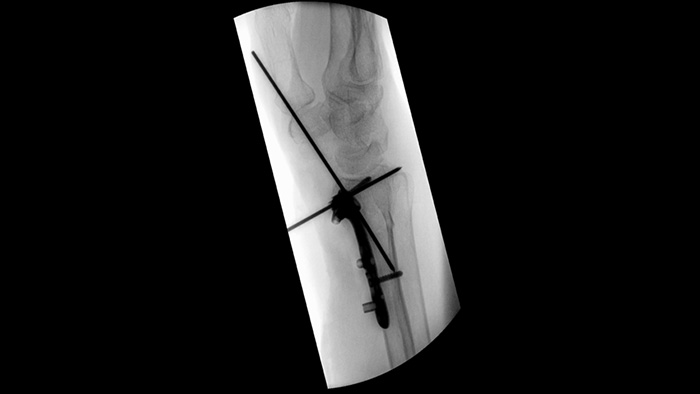

ZenitionのMetalSmartは、整形外科手術で使用するインスツルメントや金属製インプラントに対して金属を自動的に除外し金属アーチファクトを低減します。これによって高画質と効果的な線量線量コントロールを両立します。また、BodySmartは測定照射野を関心領域に自動的に適応させることで適切なコントラストと線量効率を提供します。

オートフォーカスによる安定した画質により、多様な整形外科の処置に対応できます。直観的なタッチコントロールと簡便なユーザーインターフェースにより、ZenitionモバイルCアームは瞬時に使いこなしていただくことができる装置です。

Zenition 70シリーズでは第4世代のフラットディテクタは辺縁まで歪みのない画像と、さまざまな組織に対して高品質な画像を描出することが可能です。フラットディテクタは21cm×21cm、26cm×26cm、30cm×30cmの三種類選択可能で血管内治療や脊椎手術に加え、外傷や関節などの整形外科手術、泌尿器科、外科、麻酔科など幅広い領域において最高のパフォーマンスを発揮します。